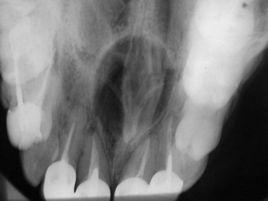

即鼻齶囊腫。也稱切牙管囊腫或鼻齶囊腫。屬面裂囊腫中常見的一種。多發生於30~59歲的男性患者。大多無臨床症狀,一般直徑不超過2cm。臨床可出現齶中線前部腫脹,可有波動感。有時囊腫向唇側生長,則引起緊貼上唇系帶下方腫脹。當有繼發感染時可使腫脹迅速增大,常伴有疼痛。鼻齶管囊腫的另一型只發生於切牙孔而不延及切牙管,稱為齶乳頭囊腫。病變囊壁上皮襯裡中有黏液細胞,結締組織中有少量淋巴細胞浸潤。又稱切牙管囊腫、鼻齶囊腫。面裂囊腫的一種,由切牙管內的胚胎上皮殘餘發生。臨床上又分為兩型:①發生在切牙孔齶乳頭處者稱齶乳頭囊腫;②起源於鼻齶管近口腔端者,襯裡為復層鱗狀上皮;來自鼻齶管的近鼻腔端者,襯裡為呼吸性上皮。囊腫位於切牙管內或其近處,X線片上可見切牙管擴大為圓形透光陰影,可自口內手術摘除。

成功的牙種植修復要求生物學和美學的雙重成功。可用牙槽骨的高度和寬度對種植體的選取和種植成功具有重要意義,在行上頜中切牙種植手術時,要求唇側和齶側都保留至少1mm的骨厚度,切牙管的存在令可用的骨組織更少。提前掌握種植區牙槽骨情況,對骨量不足者採用骨增量技術,使種植體更加穩固長久地存留在口腔內和較易獲得美學成功。切牙管位於上頜前牙區切牙孔的後上方,分別有鼻腔和口腔開口,管內有鼻齶神經血管束。